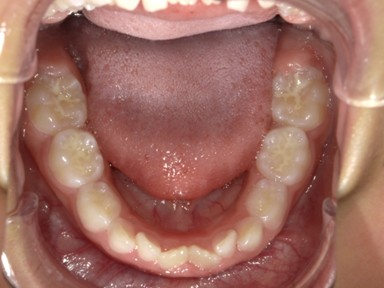

| 主訴 | 受け口を治したい。 |

| 治療内容 | ・使用装置:- マイオブレース(J1, J2) ・ワイヤー矯正および拡大装置等:未使用 ・抜歯:なし |

| 治療費 | 110,000円(税込み) |

| 治療期間 | 2017年9月~2018年8月(現在も定期的に保険にて観察中) |

| 治療回数 | 10回 |

| 想定されたリスク | マイオブレースの装着状況によっては結果が得られず、その他の矯正器具を使用する可能性がありました。 |

乳歯の反対咬合は様子を見ましょうと言われることが多いですが、上顎の前方発育を阻害する大きな要因となりますので、早期の介入をおすすめしています。反対咬合は1年で改善し、現在は定期健診で様子を見ています。装置を付けることなく、良好に生え変わりが進んでいます。